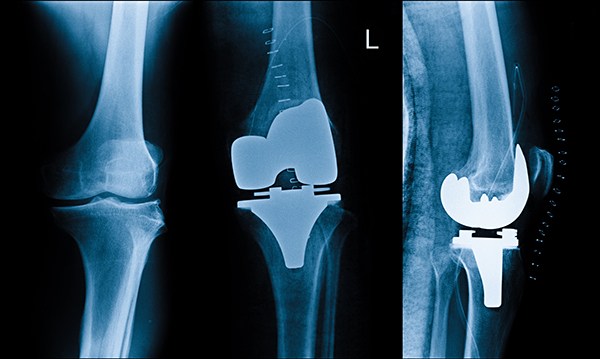

7. خضوع المريض للآشعة بصفة دورية منتظمة لتقييم حالة المفصل ومدى التئام العظام.

يتم الكشف علي المريض وعمل أشعات خاصه لتحديد نوع المفصل المناسب لكل حاله.

يتم زراعة المفصل البديل أما بشكل تقليدي أو عن طريق جراحة طفيفة التوغل، طريقة الزراعة تتعلق بالظروف الفردية والخيارات الخاصة بكل مريض على حدة، في حين أن مخاطر عامة كالعدوى أو اضطراب في شفاء الجرح أو خثرات يمكن أن تحدث، من الممكن أيضا أن تحدث مشاكل خاصة بالمفصل البديل الصناعي، في بعض الحالات يتوجب تبديل بعض المكونات أو المفصل بأكمله في إطار تغيير المفصل البديل.

فى هذه الجراحة بعد تخدير المريض, يتم إزالة الأسطح المتهالكة من عظام الفخذ والقصبة (و الصابونه فى بعض الحالات) وإستبدلها بأجزاء صناعية بحيث يختفي الألم الناتج عن إحتكاك العظام ببعضها ويزداد مدى الحركة فى الركبة وتستغرق الجراحة عادة ما بين 60 – 90 دقيقة على حسب صعوبة الحالة والنوع الذي يعتمد علي سعر الركبة الصناعي ومن مزايا هذه الجراحة أن أي أعوجاج (تقوس) بالساق يتم إصلاحه من خلال الجراحة نفسها ويستطيع المريض المشي على رجله فى اليوم التالي للجراحة مباشرة بمساعدة عكازات. ويمكن إجراء هذه الجراحة من خلال جرح صغير كما أن هناك تقنيات حديثة مثل المفصل ثلاثي الأبعاد تستخدم فى بعض الحالات واستخدام الروبوت فى إجراء الجراحة.

ويتكون مفصل الركبة الصناعي من جزء معدني يغطي سطح عظمة الفخذ وآخر يغطي القصبة وبينهما مادة بلاستيكية بيضاء ذات قوة عالية لمنع الأحتكاك بينهم وفى حالات قليلة قد يتم تركيب جزء بلاستيكي يغطي سطح عظمة الصابونة (الردفة) ويتم تثبيت هذه الأجزاء فى العظام عادة بواسطة مادة تسمى الأسمنت العظمي وهناك انواع من مفاصل الركبة الصناعية يتم تركيبها بدون أسمنت طبي ولكن إستخدامها غير شائع نظرا لإرتفاع تكلفنها وعدم ثبوت تميزها عن المفاصل الأسمنتيه.

تعتبر جراحة مفصل الركبة الصناعية من الجراحات المكلفة بعض الشيء وذلك نظرا لتضمنها ثمن المفصل الصناعي نفسه والمستلزمات الخاصة بتركيبه وبصفة عامة يقوم الطبيب بتقدير تكلفة عميلة تغيير مفصل الركبة في الحبيب بعد فحص المريض والإطلاع على أشعاته لتحديد نوع المفصل المناسب لحالته تكلفة عملية الركبة الصناعية. تكلفة عملية الركبة الصناعية